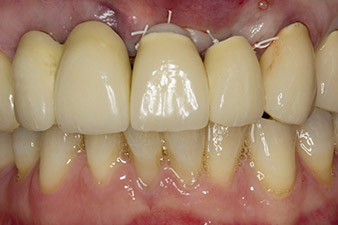

След първичното оздравяване, меките тъкани са оформени посредством базално разположения мост. Два месеца по-късно, обработваното поле е изложено на палатинална алвеоларна инцизия (Фиг 2). Размерите на алвеоларната кост са достатъчни в позиция 22. Фигури 2 и 4 показват препарацията на имплантното ложе, нарязващия винт и имплатирането, използвайки Implantmed.

С цел да се компенсира периодонталната загуба на кост и да се постигне естетически добър резултат, имплантирането е комбинирано с водена костна регенерация (GBR) с ксеногенен заместващ материал и колагенова мембрана (Фиг. 5 и 6).